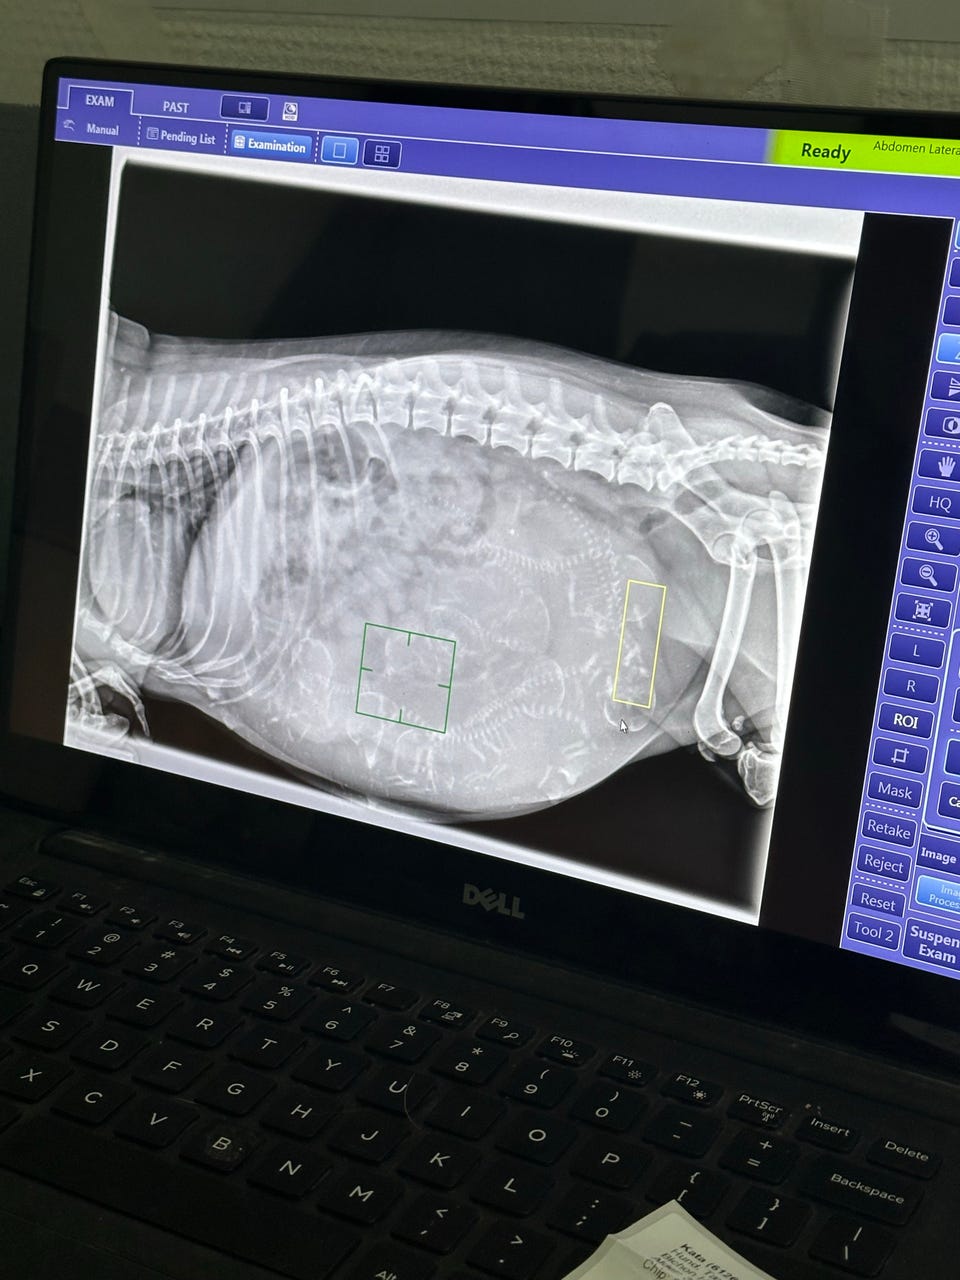

Havanais hvalpe søger nye madskåle 🐾 Vi har den store glæde at vi forventet 9 dejlige hvalpe af racen Bichon Havanais – med Ddh stambog. Hvalpene bliver født i trygge og kærlige omgivelser med stor fokus på tidlig socialisering, miljøtræning og korrekt prægning. Vi lægger vægt på at give dem det bedste fundament for et trygt og harmonisk familieliv. De vokser op midt i vores hjem(køkken-Stue), hvor de dagligt socialiseres af både børn og voksne. De bliver vant til håndtering, hverdagens lyde og får masser af kærlighed ❤ ️Hvalpene er efter racetypiske og sundhedstestede forældre, med et kærligt temperament og stærke linjer. Begge forældre opfylder Ddh racens Krav og anbefalinger for sundhedsundersøgelser. ✨ Sundhed: · Ddh stambog · Sundhedsundersøgt af dyrlæge · Vaccineret · Chippet/ Id-mærket, chip med temperatur måler · Registreret i Dansk Hunderegister · Ormebehandlet efter anbefaling (når de er 3-5 og 7uger) 🐶 Racen: • Bichon Havanais er en kærlig, glad og intelligent selskabshund. Racen er kendt for sit milde temperament, sin store tilknytning til familien og sin allergivenlige pels (dog kræver den regelmæssig pleje). De egner sig både til børnefamilier, par og seniorer. Bichon Havanais er en hengiven, intelligent og livsglad selskabshund med et venligt og stabilt sind. Racen er velegnet som familiehund. 🏡 Vi søger: • Kærlige og ansvarlige hjem, hvor hvalpen bliver en del af familien. Vi forbeholder os retten til at vælge mellem interesserede, da det vigtigste for os er det rette match. Hvalpene er klar til at finde nye madskåle fra ca 2/5-26 Hvalpen med Ddh Stambog + og Ddh s købsaftale. Der medfølger en hvalpepakke med b.la. foder til de første dage, bamse med duften af mor og søskende. Vi glæder os til at høre fra jer og til at finde de helt rigtig familier .